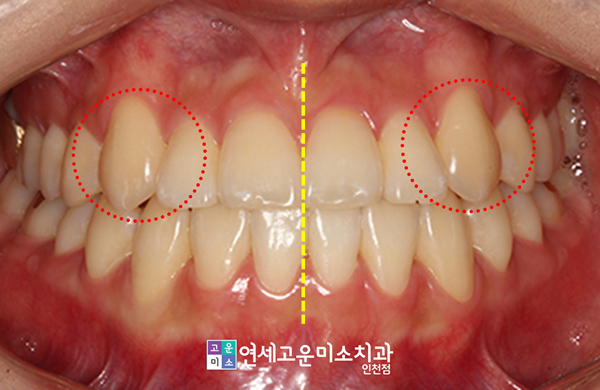

송곳니 위치 기준으로 볼 때, 앞니가 많이 나와 있었습니다. 턱뼈 자체의 전후적 부조화가 좀 심한 것처럼 보였는데요.

이로 인해 어금니 쪽에서도 위아래 치아가 같은 라인에서 맞닿는 현상이 나타났습니다.

또한 아랫니가 상악 앞니를 지속적으로 누르게 되면서 상대적으로 양쪽의 송곳니가 튀어나온 것처럼 보였는데요.

게다가 하악 전치부에서도 치아가 한쪽으로 기울어져서 다른 곳과 겹쳐지게 되었고, 이것이 덧니로 이어졌습니다.

뿐만 아니라 중심선도 다소 비뚤어진 것으로 보였는데요. 이러한 문제들을 종합하여 치료계획을 마련하였습니다.

상악 송곳니도 알맞은 위치에 적절하게 배열되었습니다. 중심선도 정확히 일치시켰죠.